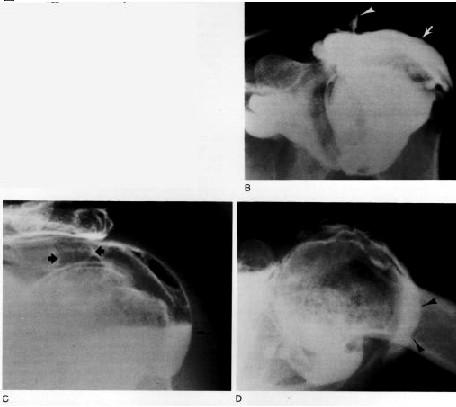

Artrografía…

Indicaciones de la Artrografía • Ruptura del Maguito de los Rotadores • Capsulitis Adhesiva • Alteraciones del Tendón del Bíceps • Luxaciones Crónicas • Evaluación de Inflamación Sinovial • Hombro Congelado

Artrografía